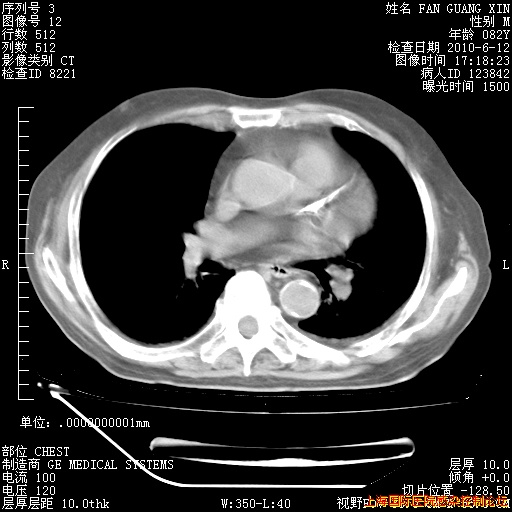

今天复查CT

今天CT

整整相隔30天的肺部CT好像有所好转啊。甲强龙减量第3天,需要观察体温。

海管,自昨日你和我通完话后,不知您岳父消化道症状有无缓解?体温怎样?阅读7.12日胸部ct,个人认为目前激素治疗是有效的,甲强龙减量是适宜的。因在抗痨治疗,需密切观察肝功、肾功能和血常规。不过,老年、长期住院和大量使用激素,很担心菌群失调发生